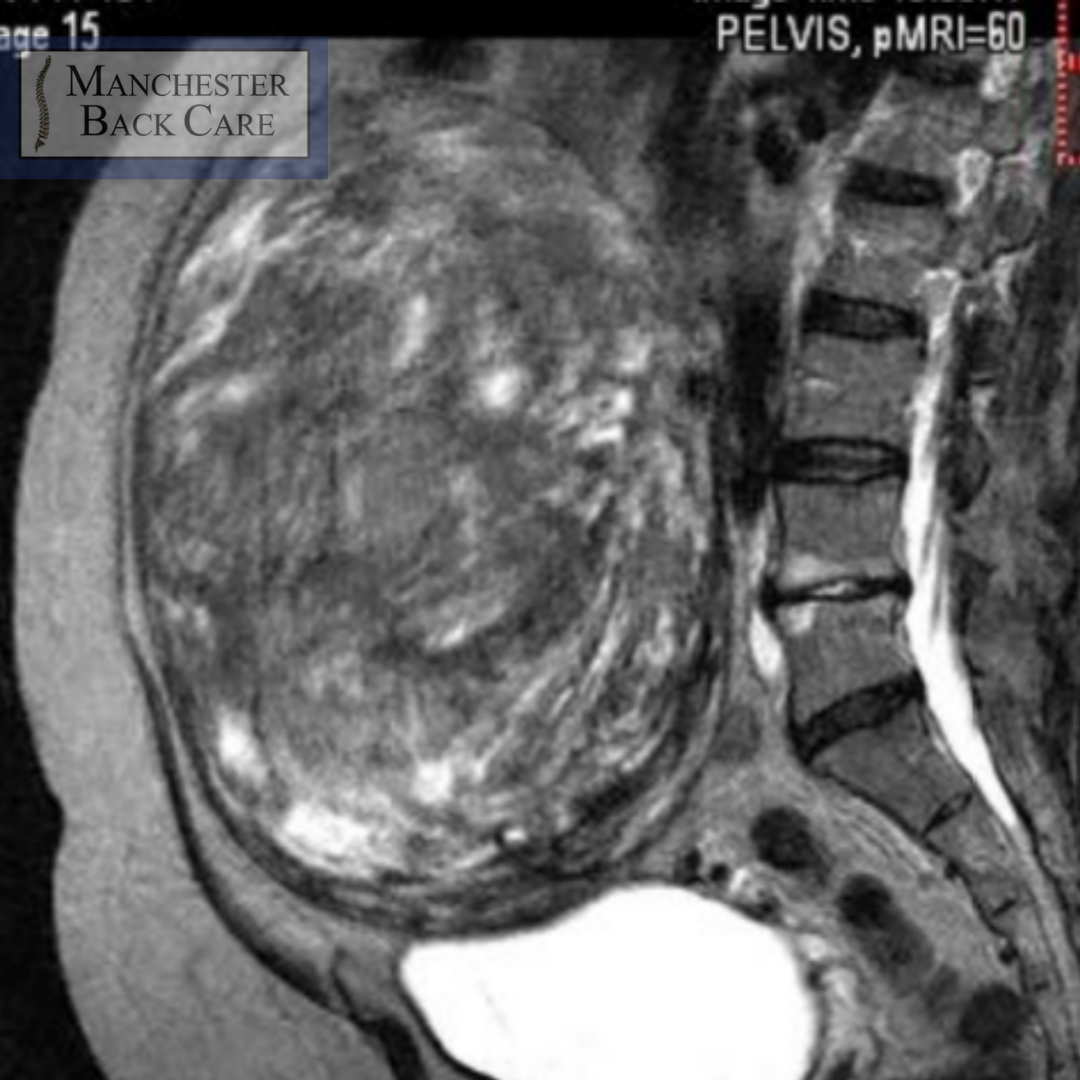

One such fascinating example of the human body’s apparent impertinence towards “the norm” is shown above with the kind permission to display it from one of my patients. At first glance you easily see the outline of the lumbar spine side on. If you look in front of that, then you should be able to make out a very large and grey egg-like structure that spans from the height of the entire lumbar spine and projects forwards. What you re seeing is a relatively common condition – Fibroids.

This particular example is that of only one solitary fibroid and this particular one is gigantic! Certainly the biggest one I’ve ever come across.

I’m sure many women reading this may well have had fibroids in their lifetime- they are, on the whole, common with around 1 in 3 women developing them. These non-cancerous growths can vary in size from tiny to this which is comparable to a 5 month old foetus or, for fruit fans out there, a Honeydew Melon.

And what makes this even more fascinating is that the lady in question is, for the most part, asymptomatic despite it! I find it so

incredible to think that something this large and seemingly so invasive to our bodies can be so inconsequential.